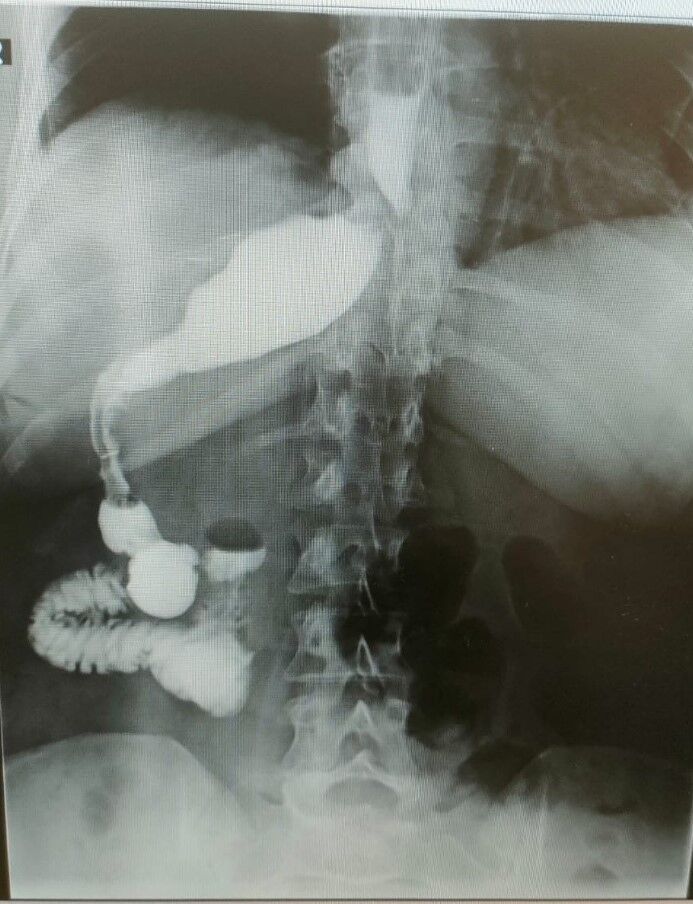

Antalya’da özel bir hastanede gerçekleştirilen operasyon sırasında Kirscht’in midesini olması gerektiği yerde göremeyen doktorlar kısa süren şaşkınlığın ardından mideyi karaciğerinin arkasında, sağ tarafta buldu. Mide başarılı bir operasyonla küçültülürken bu sıra dışı anatomik durumun, dünyada yalnızca 100 binde bir görüldüğü biliniyor.

Almanya’da hemşire olarak görev yapan Antje Kirscht, tüp mide ameliyatı olmak için sosyal medyada yaptığı araştırmalar sonucunda Memorial Antalya Hastanesi Genel Cerrahi Bölüm Başkanı Prof. Dr. Alihan Gürkan’a ulaştı. İlk kez Antalya’ya gelen 46 yaşındaki Kirscht, 110 kilo ağırlığıyla obezite tedavisi için başvurdu. Almanya’da kendisine organlarının ters olabileceği yönünde bir tanı konduğunu ifade eden Kirscht, bu bilginin ameliyat sırasında ne anlama geldiğini öğrendi. Ameliyat esnasında cerrahi ekip, Kirscht’in midesini karaciğerinin arkasında, sağ tarafta buldu. Bu sıra dışı anatomik durum, hem hasta hem de ekibin şaşkınlık yaşamasına neden oldu.

Ameliyatı gerçekleştiren Memorial Antalya Hastanesi Genel Cerrahi Bölüm Başkanı Prof. Dr. Alihan Gürkan, yaşadıkları şaşkınlığı şu sözlerle dile getirdi: “Çok yapılan bu operasyonlar içerisinde hastanın değişik bir anomalisi vardı. 100 binde bir görüldüğü söyleniyor. Organların hepsi ters olabiliyor. Bu daha sık görülen bir şey ama bu hastada bütün organlar yerli yerinde ama sadece mide sağ tarafa kaymış. Yani karaciğerin arkasına gitmiş. Operasyona başladığımızda mideyi bulamadık. Karaciğeri kaldırınca mideyi sağ tarafta gördük. Bu çok nadir bir durum. 2023 yılı verilerine göre, böyle bir tüp mide ameliyatı dünyada yalnızca 50 kişiye uygulanmış. Biz de bu vakayı başarıyla gerçekleştirdik. Teknik açıdan bizi zorlayan ancak deneyimimizi artıran bir ameliyat oldu”.

Prof. Dr. Gürkan, ameliyatın detaylarına değinerek, “Tüp mide operasyonunun ayna görüntüsünü yaptık. Normalde sol tarafta yaptığımız obezite ameliyatını bu hastada sağ tarafta gerçekleştirdik. Midenin karaciğerin arkasında olması ameliyat süresini 15 dakika uzattı ve toplamda 1 saat sürdü. Bizim için de hoş bir tesadüf oldu” diye konuştu.